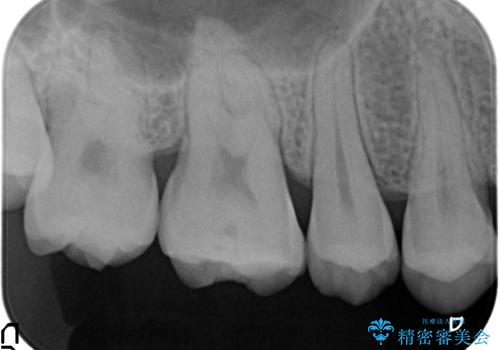

- 右上6番目の歯がしみるので診て欲しいといらっしゃった方の症例です。

古い樹脂が欠けており、そこから虫歯になっていたため、PGA(ゴールド)インレーによる修復を行いました。